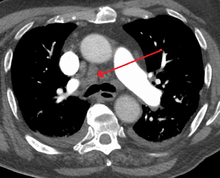

A transverse section of the thorax, showing the contents of the middle and the posterior mediastinum.